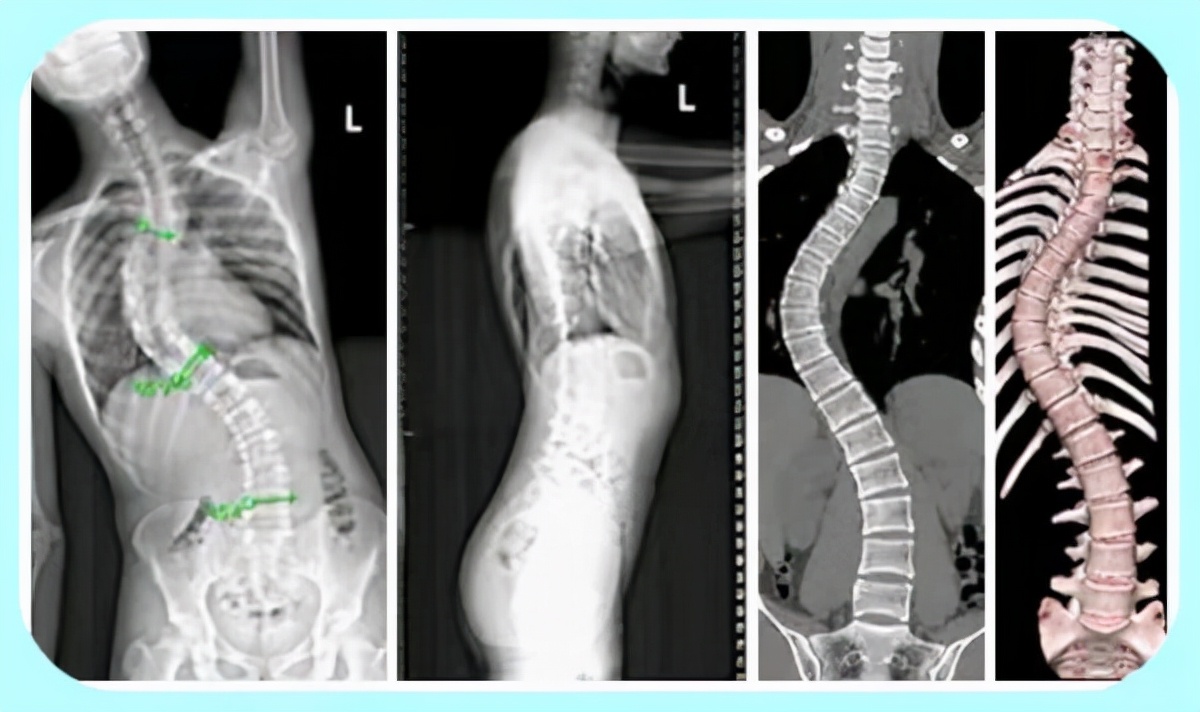

l脊柱侧弯

看点半椎体切除联合楔形截骨治疗青少年严重僵硬先天性侧后凸畸形